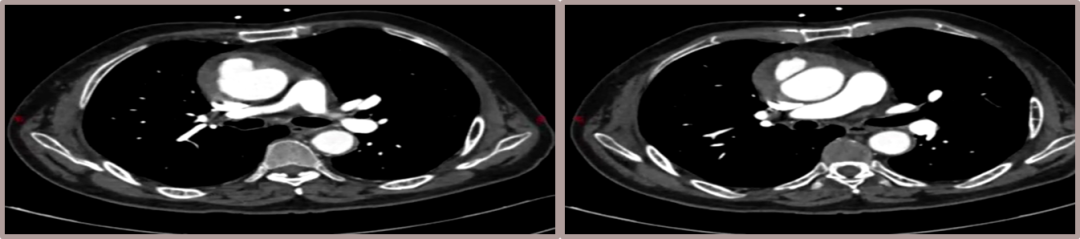

★ Case 5

男性,79岁,胸痛10+天

既往史:既往诊断高血压,未规律服药及监测血压

个人史:吸烟40余年,日均20支

头颈部CTA提示:颅内大脑后动脉P2段重度狭窄

夹层动脉瘤CTA:升主动脉局限性夹层、主动脉壁内血肿合并穿透性溃疡

术前影像